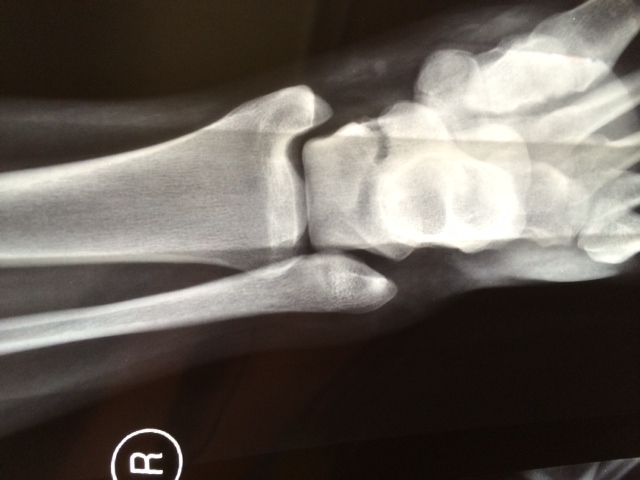

The assessment and management of lateral ankle ligament injuries

The assessment and management, as well as the clinical examination, special investigations and treatment of sports-related lateral ankle ligament injuries, are summarised for the general practitioner. Practical advice is discussed, when identifying and diagnosing chronic ankle injuries, and subsequent referral for specialist involvement.